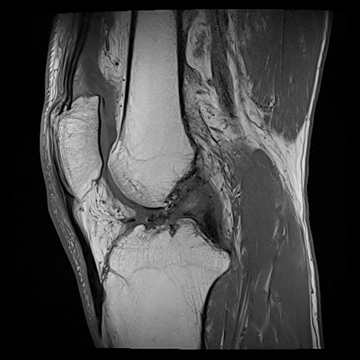

膝関節

PD 脂肪抑制

T1 TSE

3D TrueFISP脂肪抑制